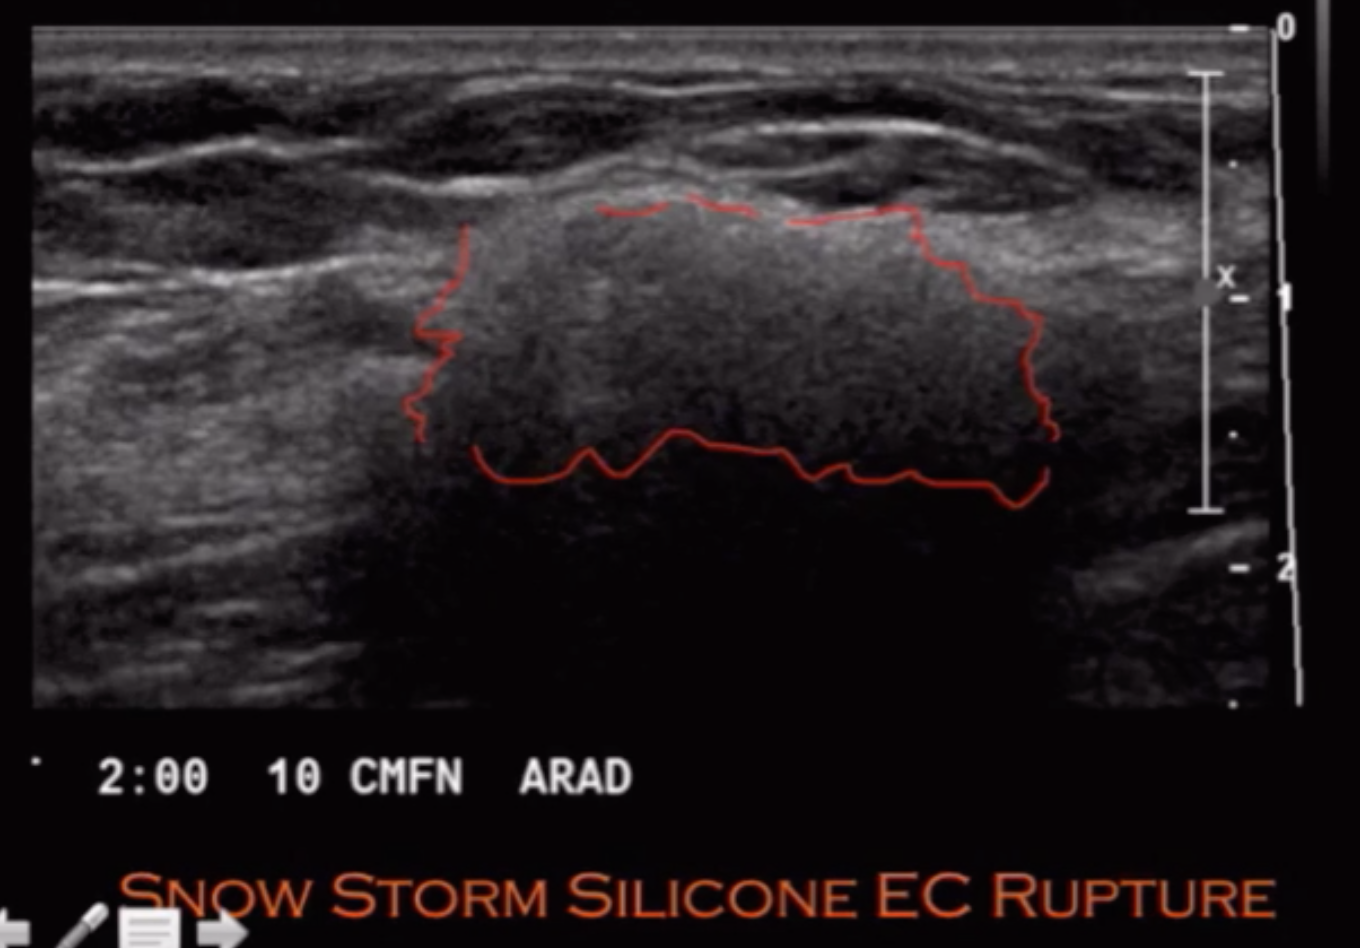

• Extracapsular rupture (20%) - Image 2

• Implies intracapsular + extracapsular

• Cannot have extracapsular rupture alone

• Injury violates the soft tissue capsule and container of the silicone implant

• Snowstorm appearance on US - looks like dense blob